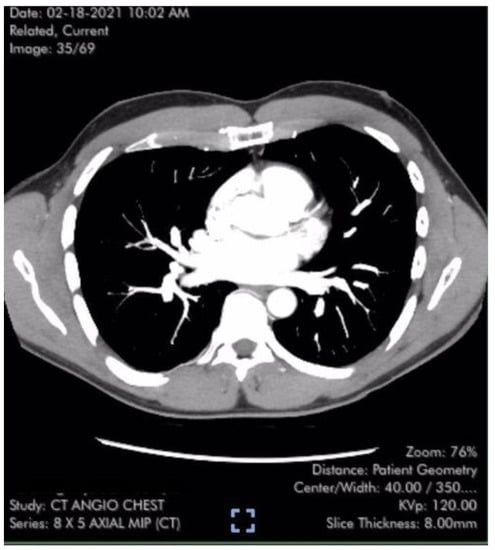

| Evidence of Pulmonary Clots | None | None |